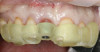

4. Facial and occlusal views of initial clinical presentation of tooth No. 8.

Figure 4

5. Facial and occlusal views of initial clinical presentation of tooth No. 8.

Figure 5